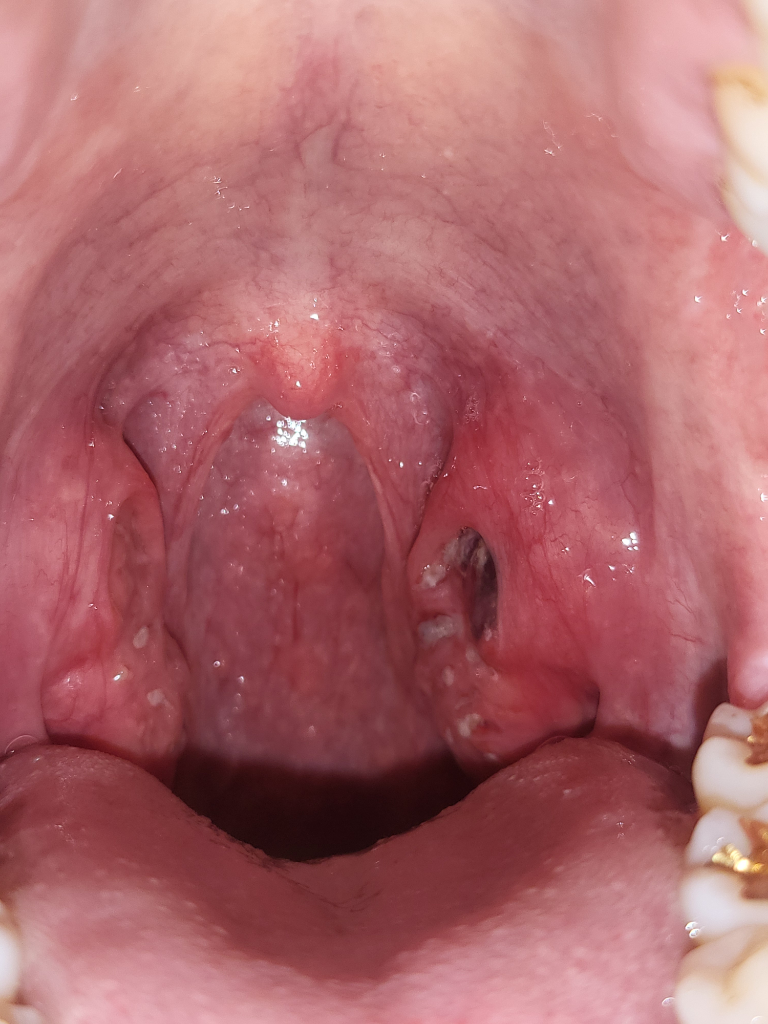

편도의 출혈에 대해 질문해 주셨는데요, 많이 걱정되셨을 것 같습니다. 답변해 드리겠습니다.

현재 편도에 부종 및 염증이 있는 것으로 생각됩니다. 출혈, 통증 등의 증상도 이를 시사합니다. 증상이 경미하다면 지켜볼 수 있지만, 불편감이 심하거나 오래 지속되는 경우에는 이비인후과 진료를 받아보시는 것이 좋겠습니다.